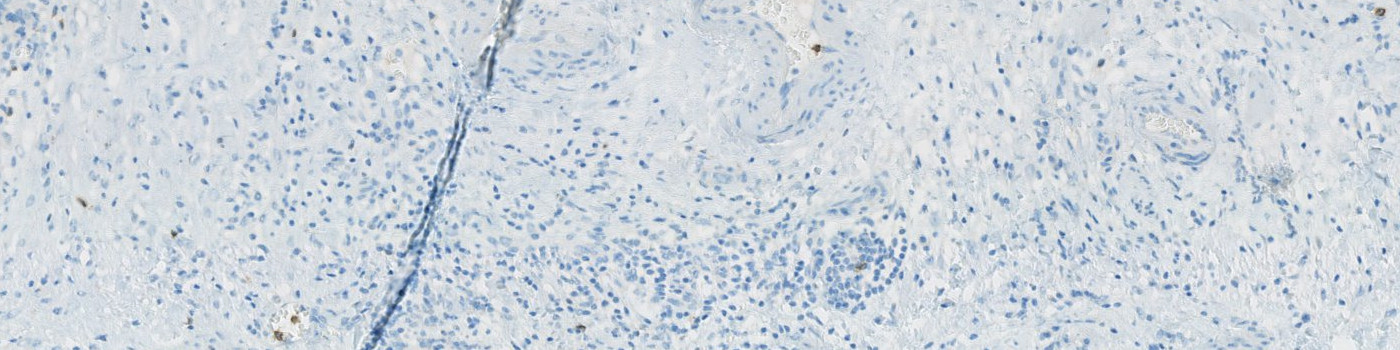

Selected view of ovarian CD57 stained tissue.

Natural Killer (NK) cells are a subtype of lymphocytes. They hold anticancer potential through tumor cell lysing and their prognostic role is being investigated in many cancers, with a perspective of a therapeutic potential. The prognostic role of tumor infiltrating NK cells in ovarian cancer, is being investigated at the Department of Clinical Pathology, Vejle Sygehus.

This APP can be used to evaluate the number or density of CD57 positive nuclei.

A NK positive cell is detected as a haematoxylin stained nucleus surrounded by DAB membrane stain. Initially, the protocol detects haematoxylin stained nuclei surrounded by brown stain using a poly blob filter on the H&E haematoxylin band and a median filter on the HDAB-DAB band. The DAB membrane stain is emphasized by a mean unsharp filter, thereby excluding blurry background stain. Then, positive nuclei are detected based on size, shape, and amount of surrounding DAB stain. Final NK cells are seen in FIGURE 2.